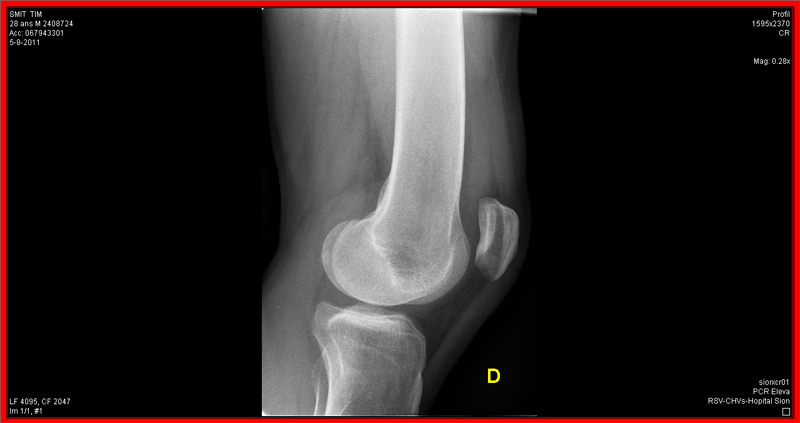

I posted some pictures on FB of a guy crashing in the Swiss mountains and getting airlifted off the mountain. Benny commented: “Danger Tim, is this you?”. Unfortunately I had to tell him yes, it is me. I had lived up to my name once again. When I visited Hobart in ’08 I met up with Benny and Mischa. After breaking my elbow in the first week (Editor: Crashed his bike) Ben and Mischa thought it would be a good idea to teach me some skills on a mountainbike and I must say, they did a fine job! (Editor: Tim failed to mention he was run-over by his own car whilst in Tassie. That particular run-in took off a LOT of bark). After the BnC Bike Bootcamp I left Tassie and went back home to mountainless Holland. Since than I’ve been showing off the BnC jersey while riding enduro races. Last week I left for a bikeholiday in Switserland with my girlfriend. Muddy forests and lack of altimeters were traded in for some serious Alpine terrain and we were loving it! On Friday I decided to take my DH-bike up the skilifts to have some fun on the trails with my friend Thomas. We had just starting going down the first decent when I completely overlooked a junction. The track curved hard right, while I was under the impression I had to go straight ahead. I hit a metal pole that was used to mark off the trail, getting launched in the air and hitting the dirt some heartbeats later. Result: dislocated kneecap, fissure in the kneecap and thighbone and a lot of pain. They flew in a helicopter to airlift me off the mountain. The French medic from the helicopter was a funny guy. He gave me a good dose of morfine and told me I would feel like I would be flying up in the air. Well, 2 minutes later I was in the helicopter so he was right about that… Yesterday I arrived back home and today they’ll take an MRI to see what the deal is with my ligaments. Hopefully I will be up and runnin asap, so I can start showing off the BnC jersey again!